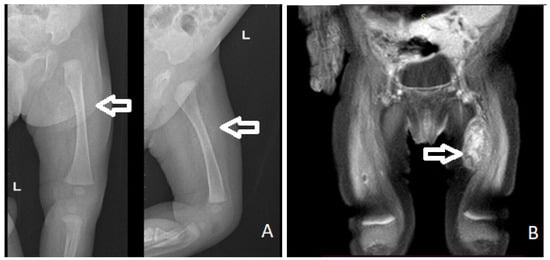

The initial X-ray and ultrasound (US) showed a pre-femoral soft tissue mass that measured approximately 30/13 mm, with nonhomogeneous structure, hypoechoic areas, calcifications, and weak Doppler signal, being located anteriorly to the vascular elements of the thigh (Figure 2A). Abdominal ultrasound was normal.

Figure 2. X-ray (A) and MRI (B) showing a mass on the antero-intern part of the left thigh (arrow).

Magnetic resonance imaging (MRI) showed a mass of 19.33/15.19/34 mm, with a nonspecific vascular involvement (Figure 2B). In T1-weighted images, the MRI appearance consisted of a low signal. In T2-weighted fat-saturated images, a high signal intensity of the lesion was shown with nonhomogeneous contrast setting after intravascular contrast was administered, but with late homogenization, located on the antero-internal part of the left thigh with an important mass effect on the left vastus intermedius muscle. The lesion was considered to be probably a schwanoma of the left saphenous nerve.